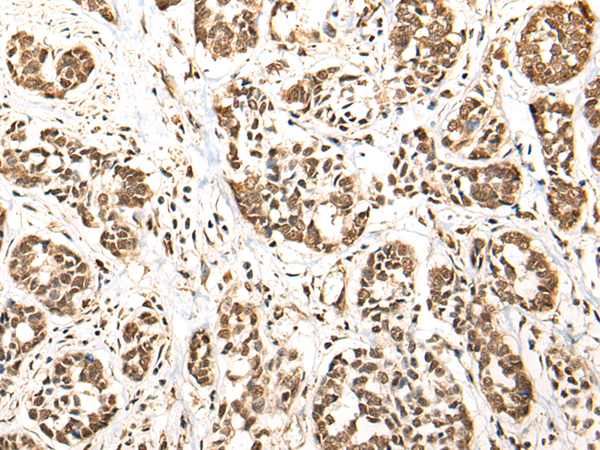

IHC positive control: |

Human liver cancer and human esophagus cancer |

IHC Recommend dilution: |

25-100 |